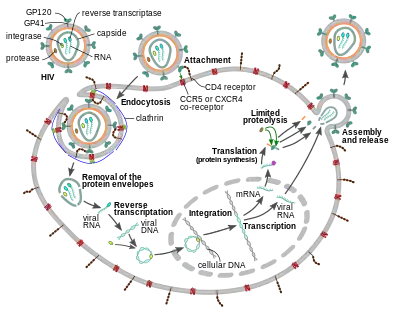

Replication cycle

Entry to the cell

The HIV virion enters macrophages and CD4+ T cells by the adsorption of glycoproteins on its surface to receptors on the target cell followed by fusion of the viral envelope with the target cell membrane and the release of the HIV capsid into the cell.[58][59]

Entry to the cell begins through interaction of the trimeric envelope complex (gp160 spike) on the HIV viral envelope and both CD4 and a chemokine co-receptor (generally either CCR5 or CXCR4, but others are known to interact) on the target cell surface.[58][59] Gp120 binds to integrin α4β7 activating LFA-1, the central integrin involved in the establishment of virological synapses, which facilitate efficient cell-to-cell spreading of HIV-1.[60] The gp160 spike contains binding domains for both CD4 and chemokine receptors.[58][59]

The first step in fusion involves the high-affinity attachment of the CD4 binding domains of gp120 to CD4. Once gp120 is bound with the CD4 protein, the envelope complex undergoes a structural change, exposing the chemokine receptor binding domains of gp120 and allowing them to interact with the target chemokine receptor.[58][59] This allows for a more stable two-pronged attachment, which allows the N-terminal fusion peptide gp41 to penetrate the cell membrane.[58][59] Repeat sequences in gp41, HR1, and HR2 then interact, causing the collapse of the extracellular portion of gp41 into a hairpin shape. This loop structure brings the virus and cell membranes close together, allowing fusion of the membranes and subsequent entry of the viral capsid.[58][59]

After HIV has bound to the target cell, the HIV RNA and various enzymes, including reverse transcriptase, integrase, ribonuclease, and protease, are injected into the cell.[58] During the microtubule-based transport to the nucleus, the viral single-strand RNA genome is transcribed into double-strand DNA, which is then integrated into a host chromosome.

HIV can infect dendritic cells (DCs) by this CD4-CCR5 route, but another route using mannose-specific C-type lectin receptors such as DC-SIGN can also be used.[61] DCs are one of the first cells encountered by the virus during sexual transmission. They are currently thought to play an important role by transmitting HIV to T cells when the virus is captured in the mucosa by DCs.[61] The presence of FEZ-1, which occurs naturally in neurons, is believed to prevent the infection of cells by HIV.[62]

HIV-1 entry, as well as entry of many other retroviruses, has long been believed to occur exclusively at the plasma membrane. More recently, however, productive infection by pH-independent, clathrin-mediated endocytosis of HIV-1 has also been reported and was recently suggested to constitute the only route of productive entry.[63][64][65][66][67]

Replication and transcription

Shortly after the viral capsid enters the cell, an enzyme called reverse transcriptase liberates the positive-sense single-stranded RNA genome from the attached viral proteins and copies it into a complementary DNA (cDNA) molecule.[68] The process of reverse transcription is extremely error-prone, and the resulting mutations may cause drug resistance or allow the virus to evade the body's immune system. The reverse transcriptase also has ribonuclease activity that degrades the viral RNA during the synthesis of cDNA, as well as DNA-dependent DNA polymerase activity that creates a sense DNA from the antisense cDNA.[69] Together, the cDNA and its complement form a double-stranded viral DNA that is then transported into the cell nucleus. The integration of the viral DNA into the host cell's genome is carried out by another viral enzyme called integrase.[68]

The integrated viral DNA may then lie dormant, in the latent stage of HIV infection.[68] To actively produce the virus, certain cellular transcription factors need to be present, the most important of which is NF-κB (nuclear factor kappa B), which is upregulated when T cells become activated.[70] This means that those cells most likely to be targeted, entered and subsequently killed by HIV are those actively fighting infection.

Assembly and release

The final step of the viral cycle, assembly of new HIV-1 virions, begins at the plasma membrane of the host cell. The Env polyprotein (gp160) goes through the endoplasmic reticulum and is transported to the Golgi apparatus where it is cleaved by furin resulting in the two HIV envelope glycoproteins, gp41 and gp120.[87] These are transported to the plasma membrane of the host cell where gp41 anchors gp120 to the membrane of the infected cell. The Gag (p55) and Gag-Pol (p160) polyproteins also associate with the inner surface of the plasma membrane along with the HIV genomic RNA as the forming virion begins to bud from the host cell. The budded virion is still immature as the gag polyproteins still need to be cleaved into the actual matrix, capsid and nucleocapsid proteins. This cleavage is mediated by the packaged viral protease and can be inhibited by antiretroviral drugs of the protease inhibitor class. The various structural components then assemble to produce a mature HIV virion.[88] Only mature virions are then able to infect another cell.